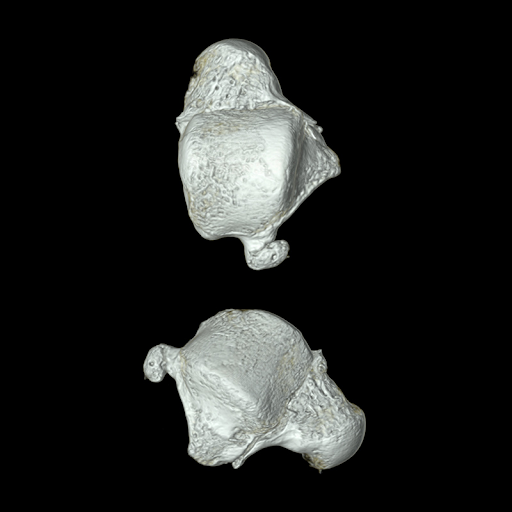

Визуализация опорно-двигательного аппарата